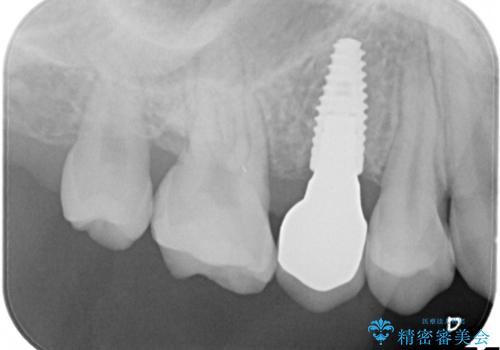

術前に矯正治療(インビザライン)を行いインプラントにて欠損補綴を行なっております。

術前に矯正治療を行うことで適正な位置でのインプラント治療が行えました。